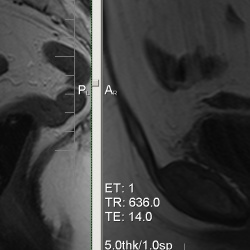

04.01.2011 - 18:53

Какие мнения будут по поводу представленных изображений?

03.01.2011 - 00:41

Большая просьба к специалистам - прокомментировать изображения.Продолжение.Продолжение.Продолжение.Продолжение.